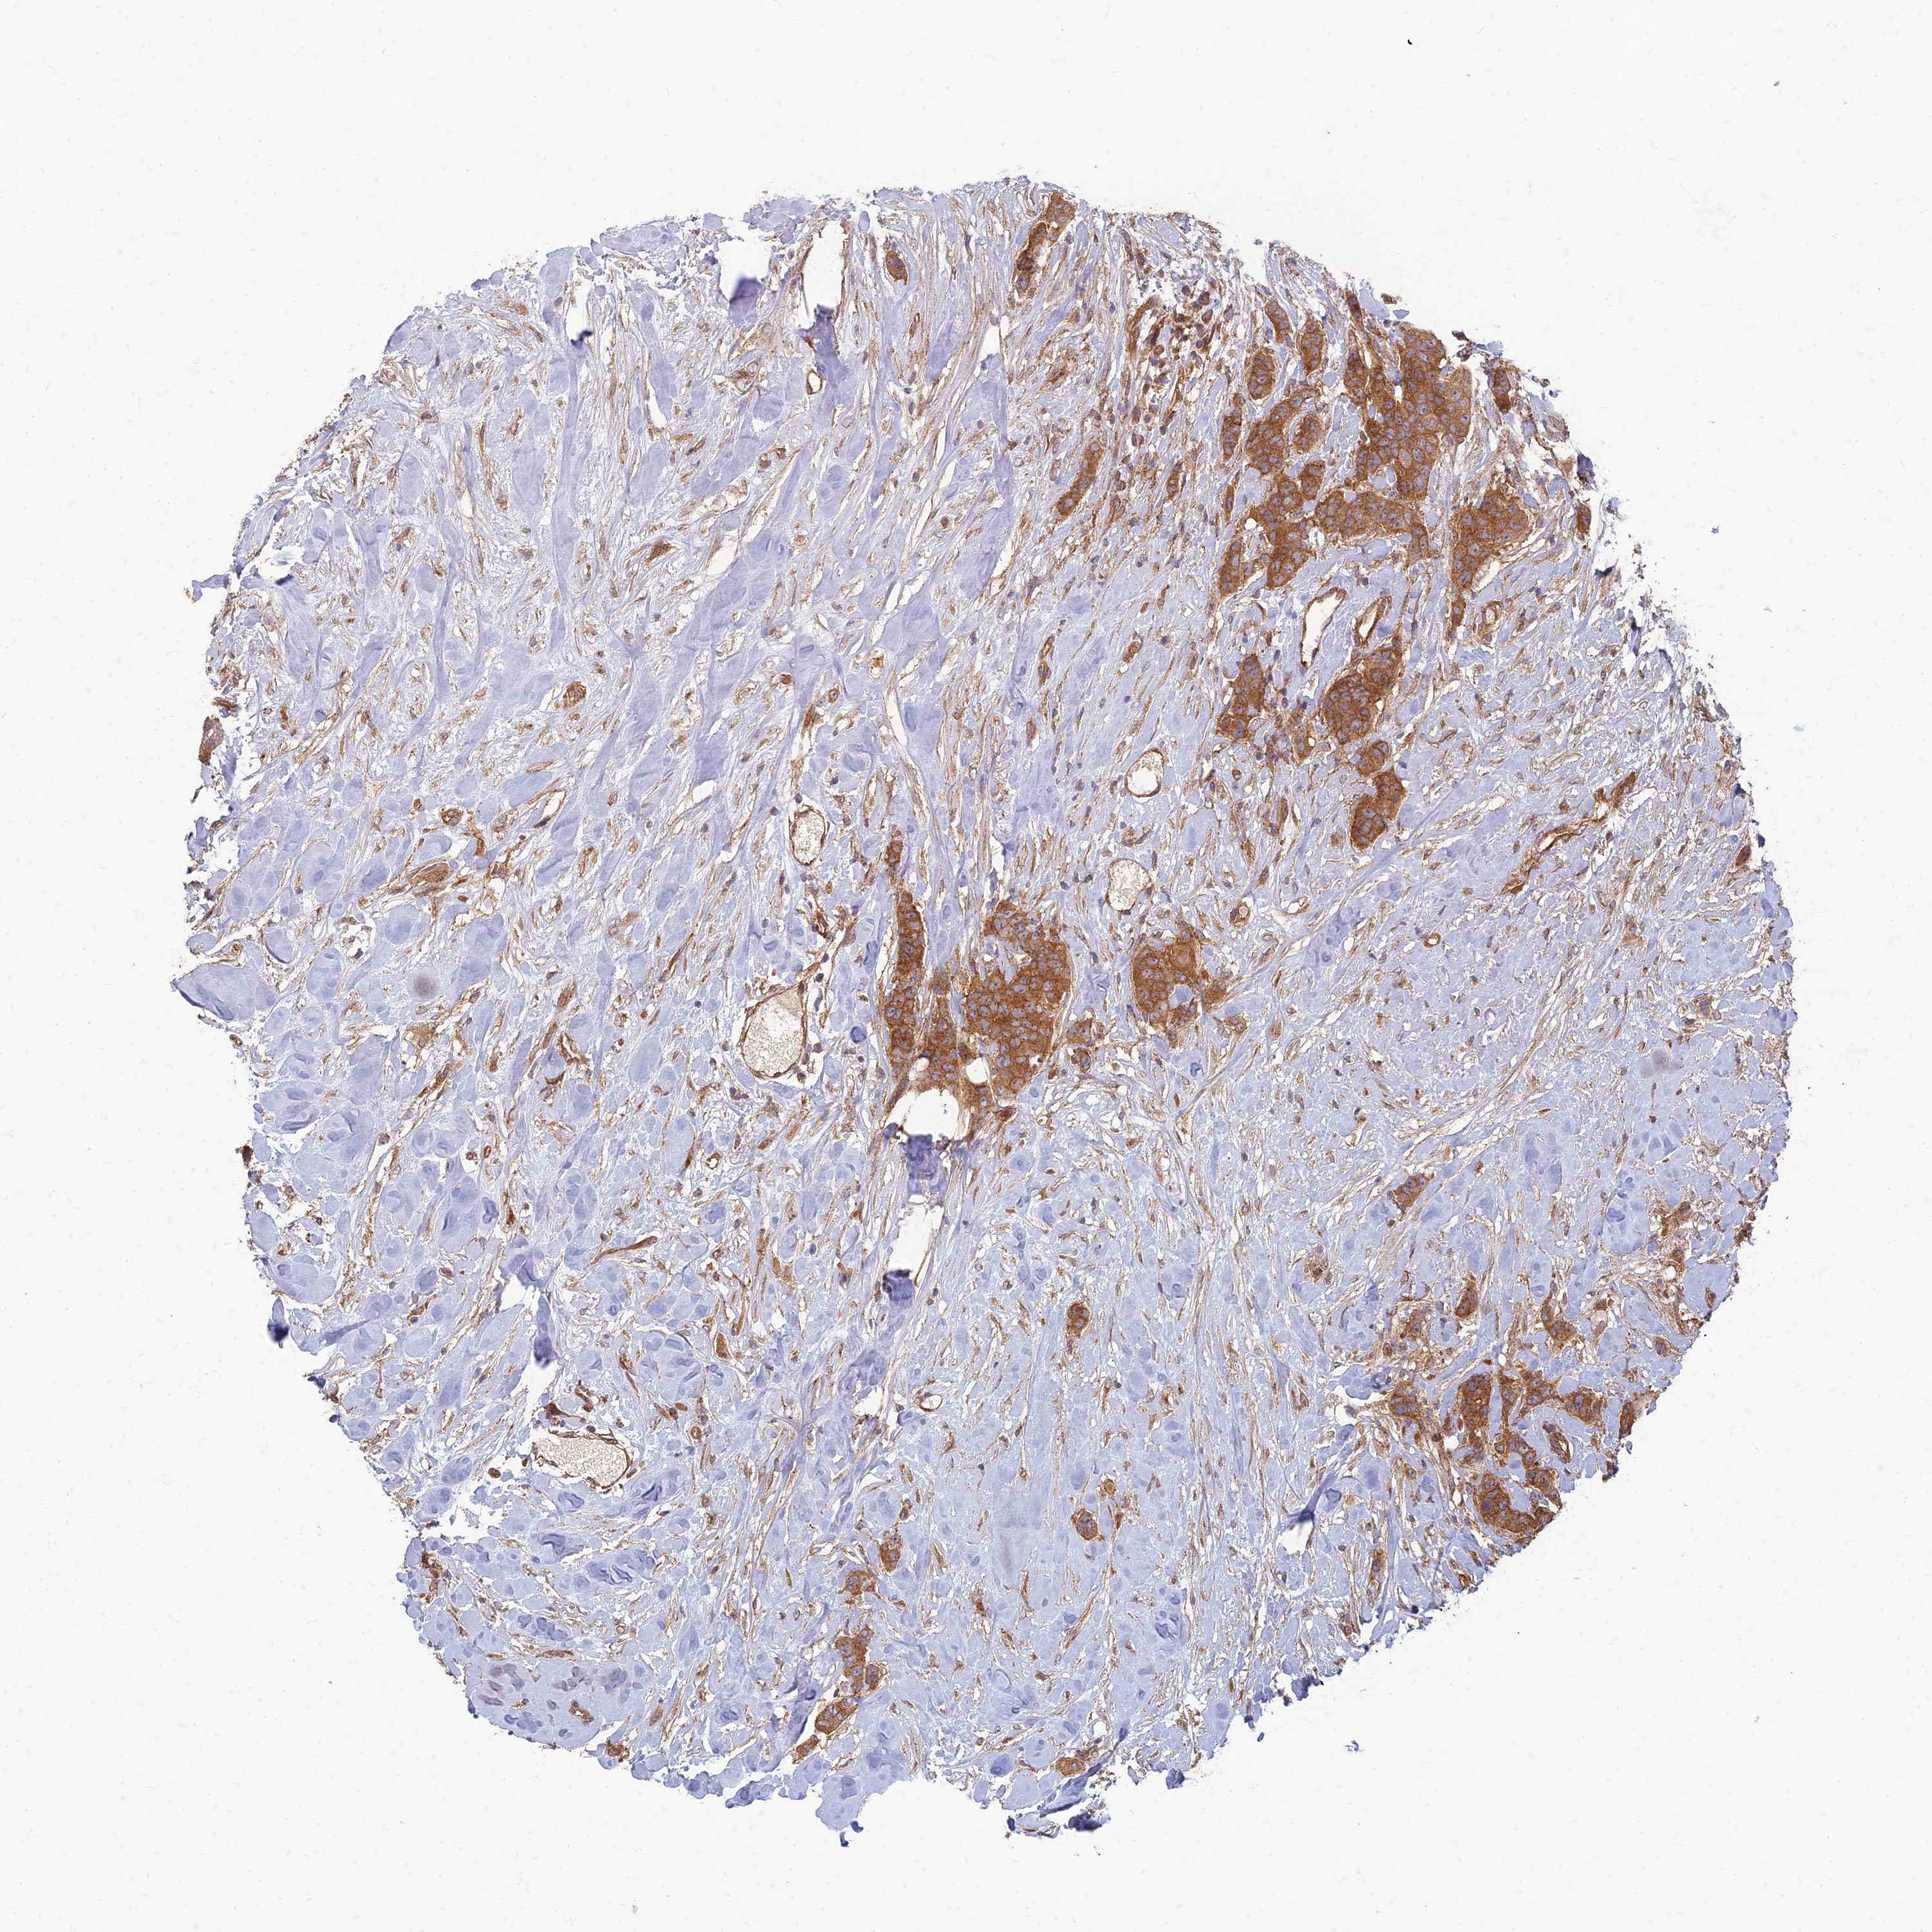

CANCER BREAST CANCER Show tissue menu

BRCA TCGA BRCA VALIDATION PROTEIN EXPRESSION